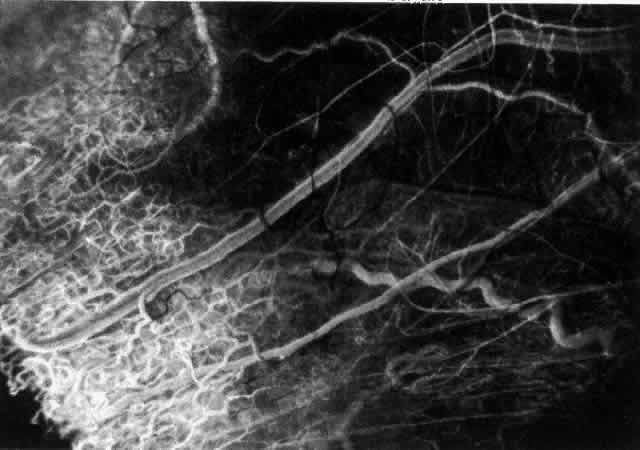

With the increasing use of anterior segment fluorescein angiography in the early detection of severe necrotizing disease of the sclera, it is necessary to have an understanding of the normal anatomy of the vasculature of the anterior segment of the eye.3–5 The blood supply to this region is enormous, being derived from the anterior ciliary arteries, but with extensive collateral arterial anastomoses to the posterior ciliary arteries at the root of the iris (Fig. 1). The anterior system is readily visible with the slit lamp and by anterior segment fluorescein angiography, especially if the eye is inflamed, and its recognition is of vital importance in the differentiation of episcleral and scleral conditions. The separation and displacement of these vascular layers give the most important clinical clues to the site and, hence, the severity of the inflammation. On slit lamp examination, three layers of vessels are readily visible. The conjunctival plexus, which is the most superficial layer of vessels, can be moved over the underlying structures. The superficial episcleral capillary plexus (Fig. 2) is a radially arranged series of vessels lying within the parietal layer of Tenon's capsule. The vessels in this layer anastomose at the limbus with the conjunctival vessels, with other members of the same plexus, and with the deep plexus. The deep episcleral capillary network (see Fig. 2) is closely applied to the sclera in the visceral layer of Tenon's capsule. The vessels anastomose freely with each other, forming a syncytium. The large vessels to and from the intrascleral plexus traverse the episclera near the insertions of the muscles. The conjunctival and superficial episcleral vessels can be blanched with 1:1000 epinephrine or 10% phenylephrine, but the deep vessels are affected slightly. This is of considerable assistance when attempting to differentiate deep and superficial inflammation.

Fig. 1. Anterior view montage of a cynomolgus monkey ocular casting with Tenon's and episcleral vessels removed. The anterior ciliary arteries (ACA) arborize at the limbus and interconnect via their lateral branches to form the episcleral circle. (CM, ciliary muscle capillary bed; CV, choroidal veins; EC, episcleral circle. (Original magnification, X20). (Morrison JC, van Buskirk EM: Anterior collateral circulation in the primate eye. Ophthalmology 90:707, 1983)

Fig. 2. The normal relationships of the capillary networks that can be seen with the slit lamp are a conjunctival (easily mobile) network, a superficial episcleral network in the parietal layer of Tenon's capsule, and a deep episcleral plexus closely applied to the sclera. These relationships are much more obvious in inflamed eyes (see Figs. 13, 14, and 30). (Watson PG, Hayreh S, Awdry P: Episcleritis and scleritis. Br J Ophthalmol 52(3):278– 279, 1968)